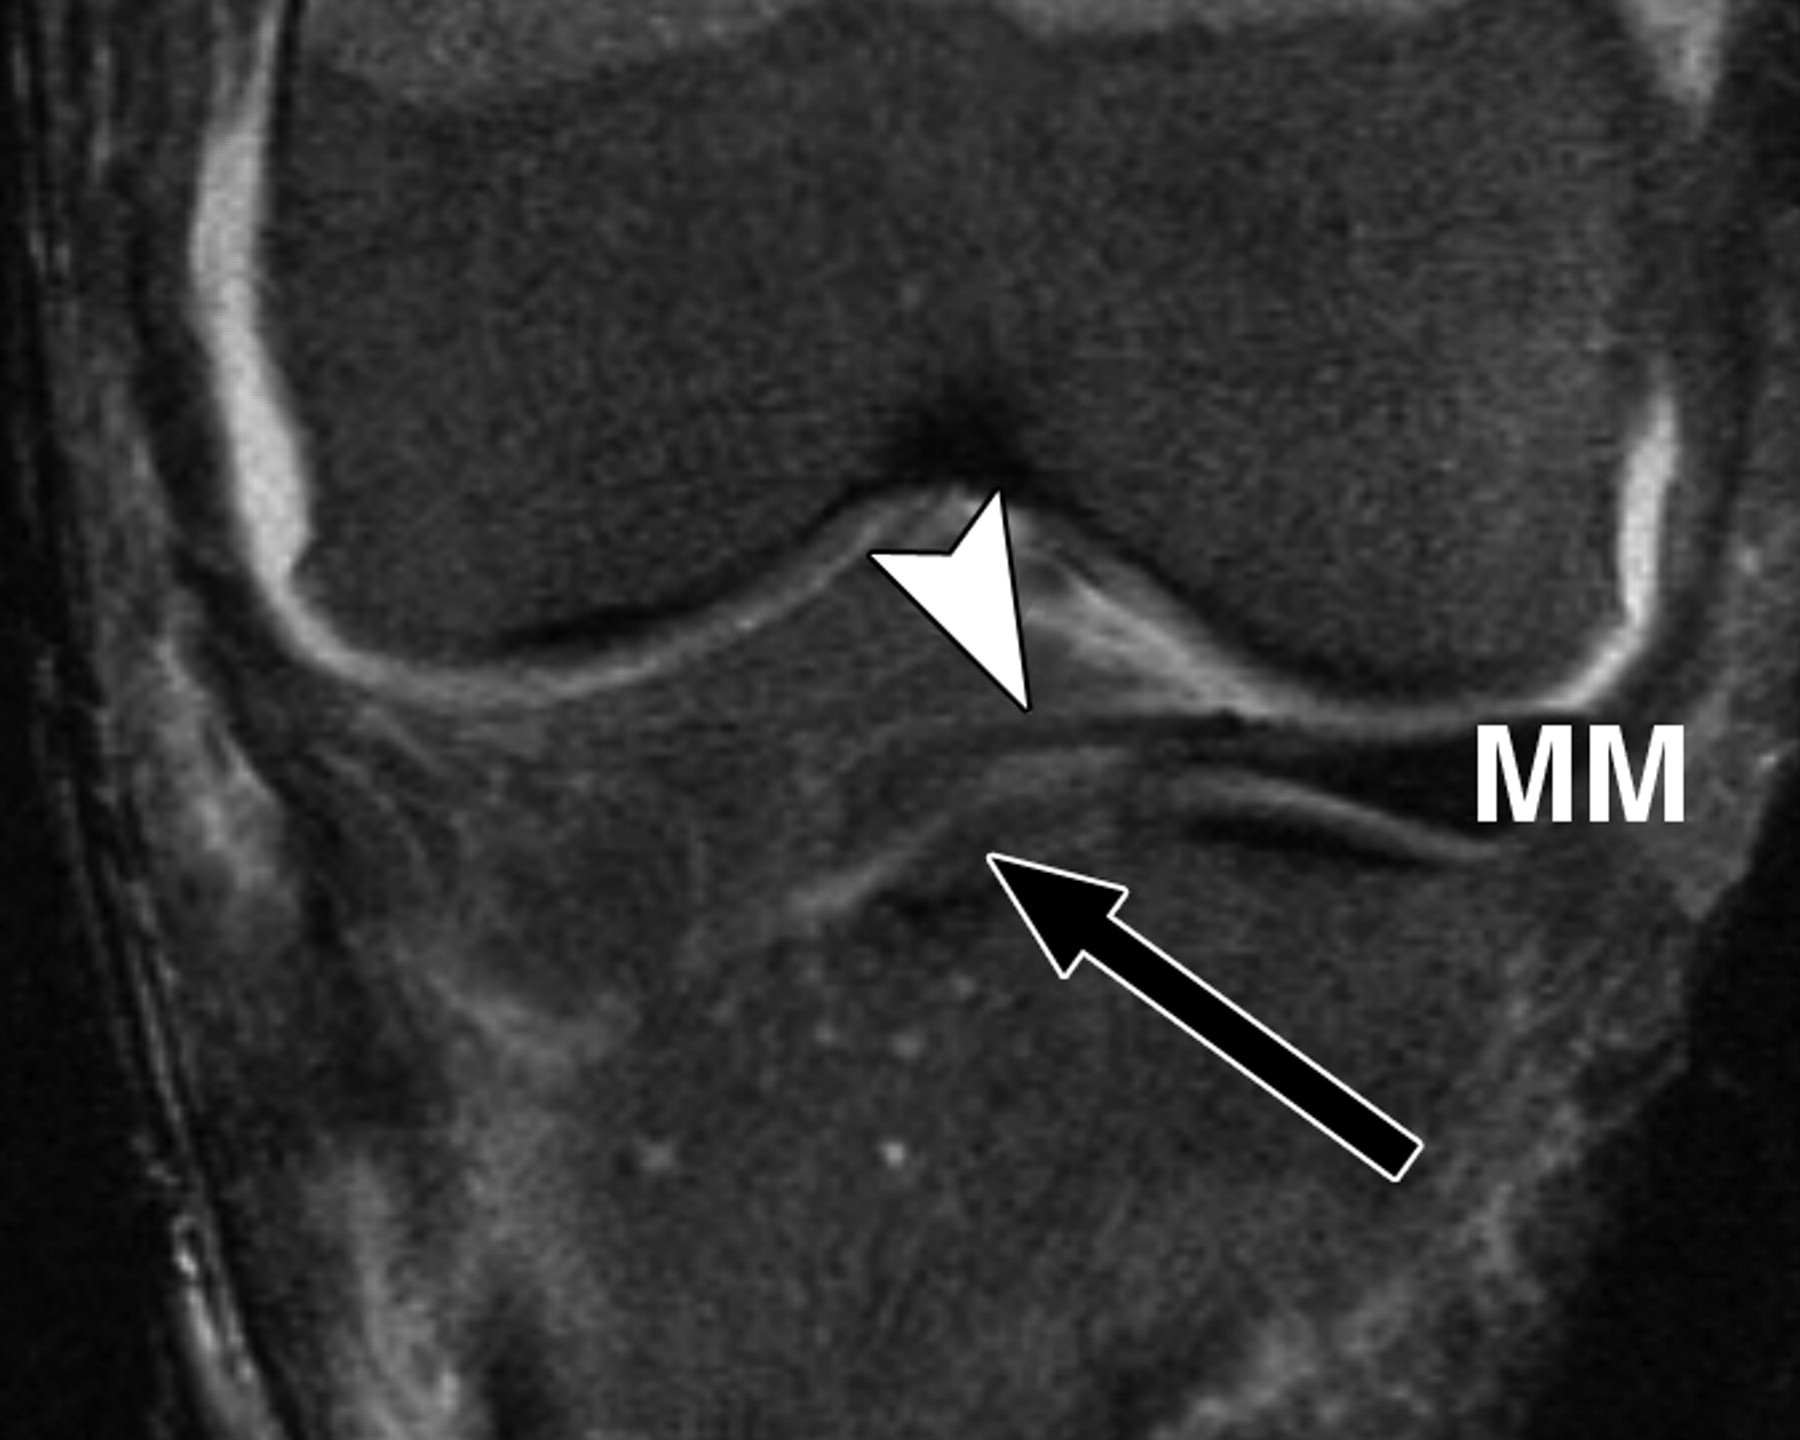

图3A-51岁女性。

膝关节的中等加权、脂肪饱和、快速自旋回波(TR/TEeff,3,700/29)3-T MR图像显示了膝关节前根、前交叉韧带(ACL)和膝横韧带的解剖关系。经胫骨前平台的冠状面MR图像显示内侧半月板前根(箭头)和膝横韧带(箭头)分离。MM =内侧半月板。